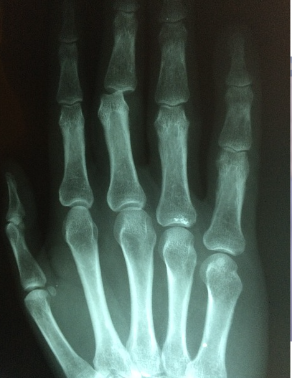

가장 대표적으로는 퇴행성 관절염이 있어요. 이는 손가락 마디 사이의 연골이 손상을 입거나 퇴행성 변화가 나타난 것을 말하는데요. 손가락 주위의 염증과 통증이 나타나고 손가락 끝마디가 예전보다 굵어지거나 돌출되는 특징도 있다고 해요. 보통 손을 자주 쓰는 직업군에서 더 잘 나타나게 되고, 손을 많이 사용하는 주부들에게서도 많이 발생하구요.

손가락 부분에 염증이 생기게 되고 갈수록 범위가 커지구요. 손가락 두번째 마디에서 느껴지는 통증이 특징이에요. 이런 부분만 봐도 다르긴한데 추가로 어떤 차이점이 있는지 알려드릴게요

퇴행성관절염과 류마티스 관절염 차이

1) 퇴행성 관절염

- 많이 사용한 관절이 붓고 아프다

- 비대칭적인 통증

- 손가락 끝마디가 아프다

- 기상시 뻣뻣한 증상이 30분 이내로 가라앉는다

- 운동 후와 저녁에 아프고 휴식으로 통증이 완화된다

2) 류마티스 관절염

- 여러 관절이 동시에 붓고 열이 난다

- 좌우대칭적인 통증

- 손가락 가운데 마디가 아프다

- 기상시 뻣뻣한 증상이 1시간 이상 지속된다

- 식욕이 줄고 쉽게 피로해진다